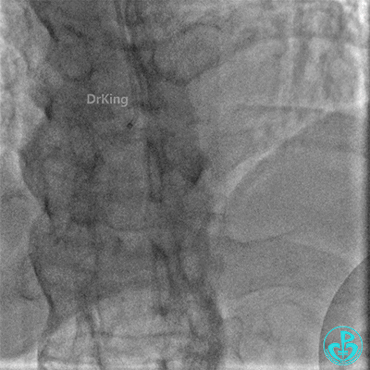

术后1小时患者诉右侧腰部疼痛、恶心、呕吐。

心率76~130次/分,血压(77~140)/(64~70)mmHg。

查体:腹部肌紧张,右侧穿刺点处有压痛。怀疑发生腹膜后血肿。

心脏超声提示少量心包积液,右下腹局限性液性区,包裹性积血不除外。